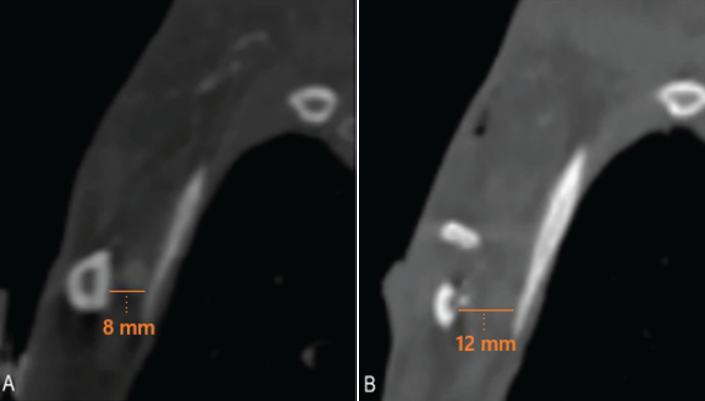

Imaging with CTA of the chest and magnetic resonance imaging of the left BP demonstrated relative narrowing of the costoclavicular space to 8 mm (Fig. 1a) and diffuse edema of the BP (Fig. 1b), most prominent proximal to the costoclavicular space. Additionally, the scapula on the left side was significantly medialized compared to the right side (Fig. 1c). Typically, the costoclavicular interval measures 12 mm [4].

Figure 1: Computed tomography angiography imaging (a) of the chest showing the normal costoclavicular interval on the unaffected right side (15 mm), (b) narrowing on the affected left side (8 mm), and (c) medialization of the left scapula noted relative to the right side, as well as narrowing of the costoclavicular interval on the left side.

The dorsal cortical rim of the clavicle was removed, as well as most of the medullary bone. This resulted in the removal of approximately 50–60% of the clavicle cross-sectional area in the region where the BP crossed. This procedure was chosen to reduce the amount of traction on the BP and relieve the stretch injury, while avoiding the morbidity of a full claviculectomy. Postoperative imaging showed the extent of the dorsal claviculectomy, especially in comparison to preoperative imaging (Fig. 4a and b). A heparin drip was resumed shortly after surgery.